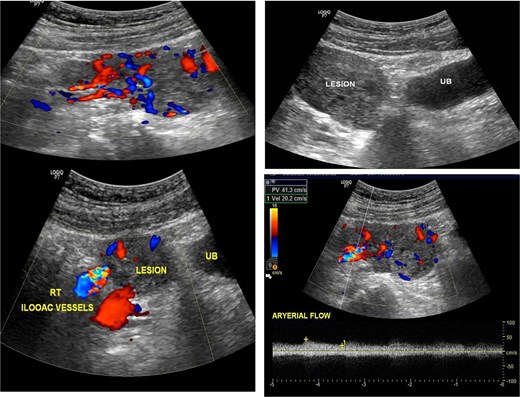

A 37-year-old man with hypertension secondary to autosomal dominant polycystic kidney disease presented to the emergency department with sudden-onset severe generalized abdominal pain and dizziness. He denied trauma, fever, hematemesis, or melena, and had no prior surgical history. On arrival, he was critically ill with hypotension (80/50 mmHg), tachycardia (120 beats/min), pallor, and diaphoresis. Abdominal examination revealed generalized tenderness with guarding and rigidity. Bedside ultrasonography demonstrated free intraperitoneal fluid and a vascular suprapubic mass separate from the urinary bladder (Fig. 1). Laboratory investigations showed leukocytosis (15 × 109/L), markedly elevated C-reactive protein (400 mg/L), elevated serum lactate (4 mmol/L) hemoglobin level (Hb 9.5 g/dL), and acute kidney injury with serum creatinine of 300 μmol/L (baseline 160 μmol/L). He was admitted to the intensive care unit with an acute abdomen and shock. Immediate resuscitation was initiated with aggressive crystalloid intravenous fluid, broad-spectrum intravenous antibiotics (piperacillin–tazobactam) and close hemodynamic monitoring.

Showed ultrasonic images revealed a large vascular heterogenous supra-pubic mass, separable from the urinary bladder (UB), the peak systolic velocity within the mass = 41 cm/s.